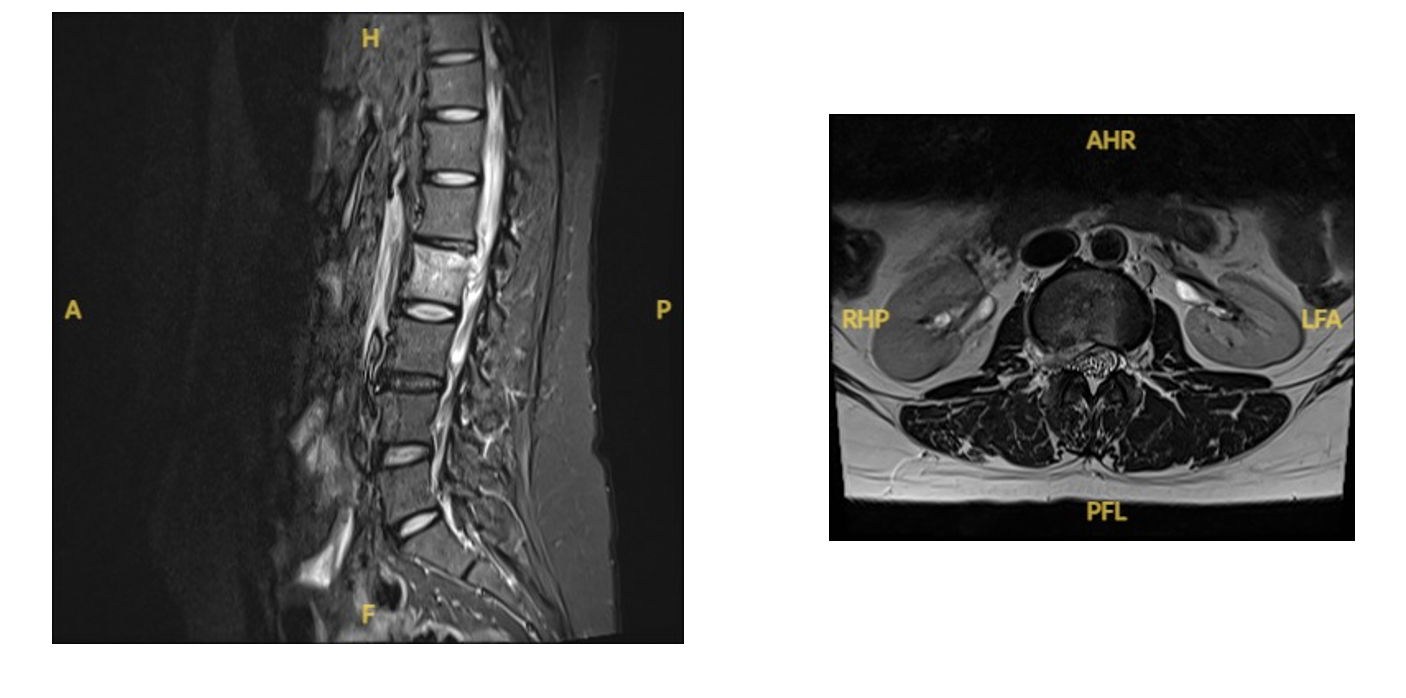

– MRI: The gold standard for diagnosing spinal infections, providing detailed images of the spine and surrounding tissues.

– CT Scan: Used if MRI is contraindicated.

– Bone Scintigraphy: Can help in early detection when other imaging is inconclusive.